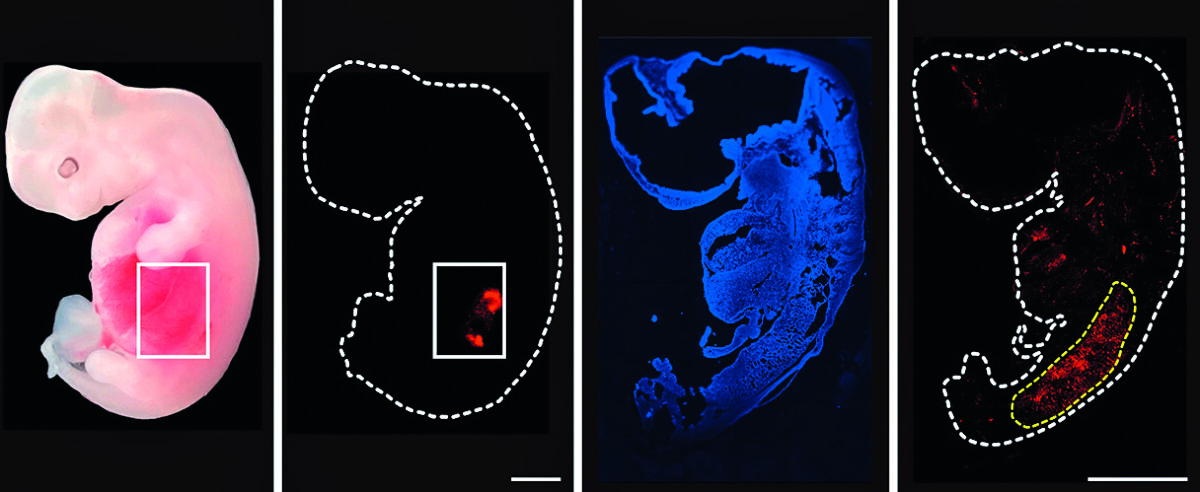

Ecco i fatti. Poche settimane fa, ricercatori cinesi del Guangzhou institutes of medicine and health, guidati dallo scienziato Liangxue Lai, per la prima volta sono riusciti a far crescere cuori pulsanti contenenti cellule umane all’interno di embrioni di maiale e ne hanno dato notizia all’International society for stem cell research tenutosi a Hong Kong. I ricercatori cinesi hanno prelevato embrioni suini, li hanno privati dei geni coinvolti nello sviluppo cardiaco e vi hanno iniettato cellule staminali umane. Rimasti in vita per 21 giorni, questi embrioni nel tempo hanno sviluppato cuori di dimensioni paragonabili a quelli negli embrioni nell’uomo.

Già nel 2023, embrioni chimerici contenenti una combinazione di cellule umane e di maiale erano stati trasferiti in madri surrogate suine dove avevano sviluppato reni. Il fatto che questi organi non fossero interamente umani non deve far pensare che quella ricerca non rappresentasse già un successo. Infatti, quei reni, se pienamente formati, potevano essere utilizzati per un trapianto nell’uomo. Quello su cui ora punta la ricerca è la realizzazione di chimere con organi umani al cento per cento. «La sfida principale risiede nella limitata capacità delle cellule umane di integrarsi e contribuire allo sviluppo dell’embrione ospite», spiega Aranguren. «In genere, le cellule umane introdotte in embrioni di suino contribuiscono in quantità molto basse: circa una cellula umana ogni 10 mila-100 mila cellule di suino. Dobbiamo capire come meglio superare le barriere interspecie che impediscono un’integrazione e una differenziazione efficienti delle cellule umane».